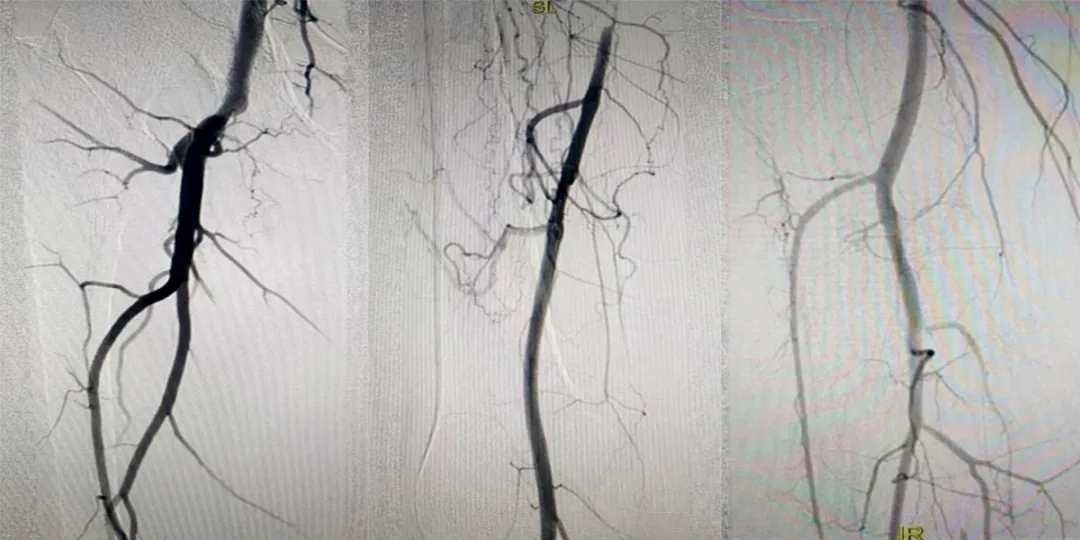

術(shù)中造影

關(guān)鍵時(shí)刻

醫(yī)生決定采用介入手術(shù)

為劉大叔開(kāi)啟“生命通道”

手術(shù)室內(nèi)

醫(yī)生們猶如微觀世界的勇士

運(yùn)用造影的“魔杖”

找到了閉塞的血管段